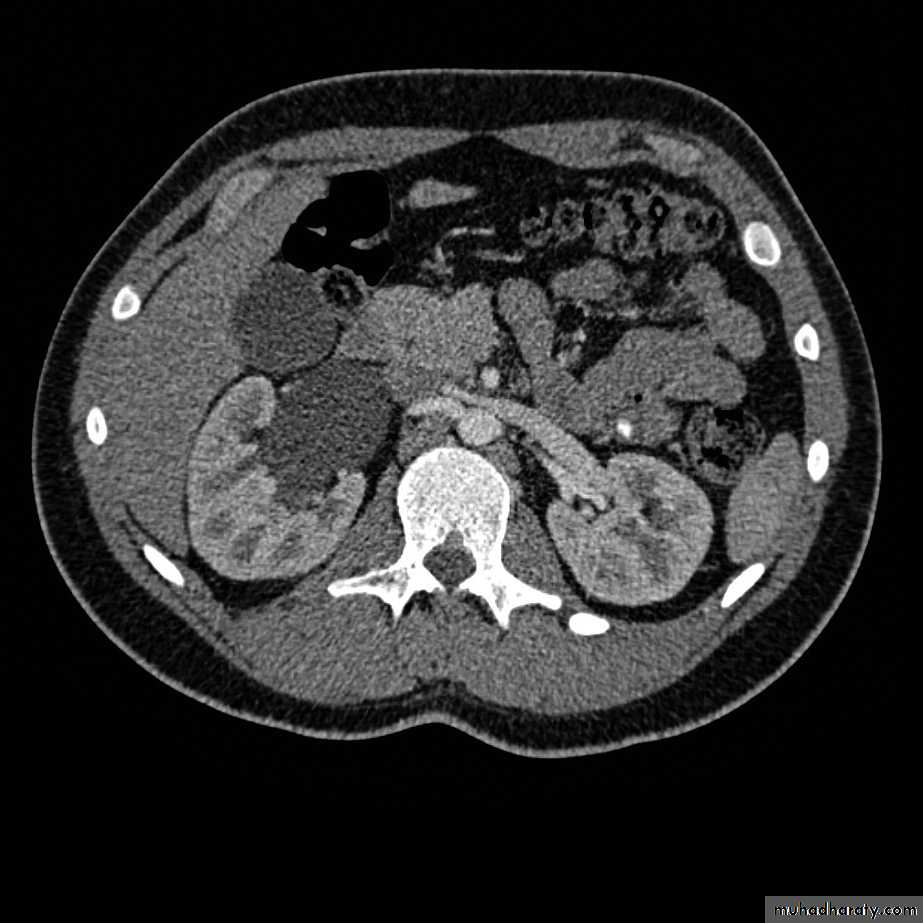

CT scanWHAT IS THE DIAGNOSIS & THE CAUSATIVE ORGANISM ?

Struvite stone ( MAP stone ).Urea splitting microorganisms.

HOW WOULD YOU TREAT HER ?PCNL